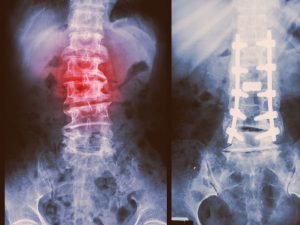

Spondylolisthesis pain, causes and treatment